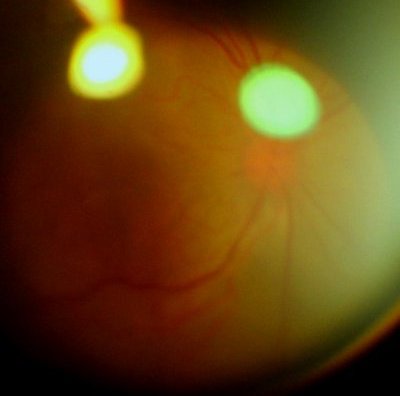

眼底:后极部视网膜渗出性脱离明显好转,后极部视网膜平伏,浅脱离,黄斑区仍然隆起。下方中周部仍可以见到隆起、皱褶脱离的视网膜。未见明显坏死灶。视网膜血管充盈扩张,右侧视乳头9点位可见线状出血

眼底像(前节照相机+90D,图像质量不高,见谅)

左眼,视网膜水肿隆起,血管充血